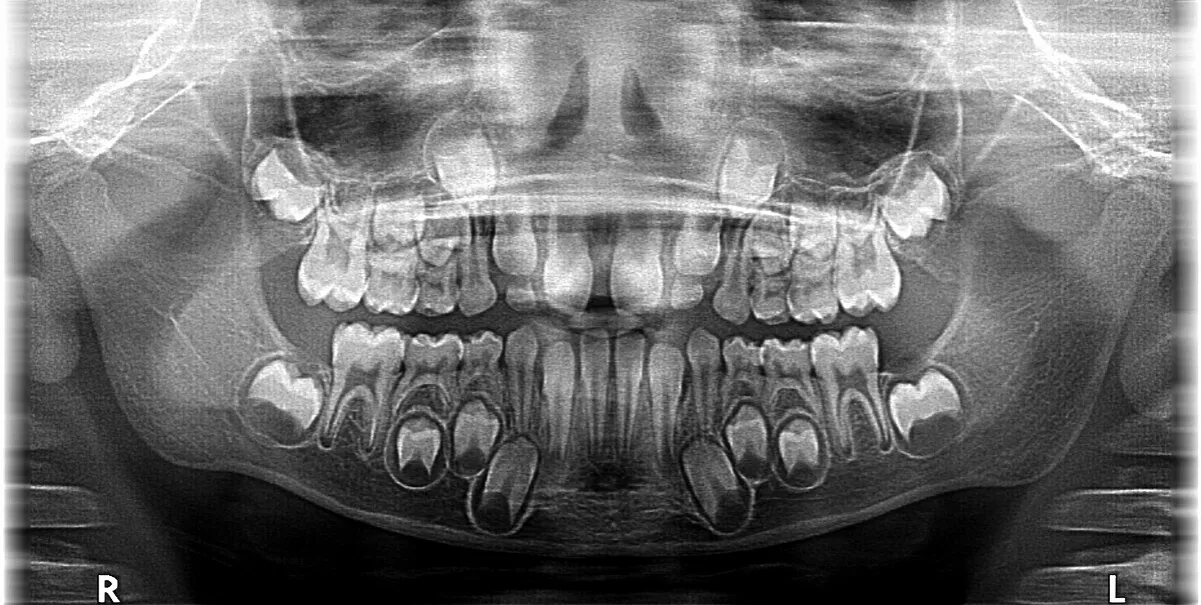

Uzębienie mieszane: Kiedy w buzi malucha spotykają się dwa światy

Okres między około 6. a 12. rokiem życia dziecka to czas, który nazywamy uzębieniem mieszanym. W tym czasie w jamie ustnej malucha współistnieją zarówno zęby mleczne, jak i stałe. Jest to zupełnie naturalna i nieunikniona faza rozwoju, która świadczy o postępującej wymianie uzębienia.

Pamiętaj, że mamy 20 zębów mlecznych i docelowo 32 zęby stałe. Pierwsze zęby stałe, które pojawiają się w jamie ustnej, to zazwyczaj siekacze i pierwsze trzonowce. Ważne jest, aby wiedzieć, że pierwsze stałe trzonowce, zwane "szóstkami", wyrzynają się za ostatnimi zębami mlecznymi i nie zastępują żadnego ząbka mlecznego. To kluczowa informacja przy ich identyfikacji.

Uwaga na "szóstki"! Jak rozpoznać pierwszy stały trzonowiec?

Pierwsze stałe trzonowce, czyli popularne "szóstki", to jedne z najważniejszych zębów w uzębieniu stałym. Niestety, często są mylone z zębami mlecznymi, ponieważ wyrzynają się w jamie ustnej dziecka w specyficzny sposób pojawiają się tuż za ostatnimi zębami mlecznymi, nie zastępując żadnego z nich. Ich prawidłowe rozpoznanie jest kluczowe.

Pierwsze stałe trzonowce ("szóstki") zazwyczaj pojawiają się około 6. roku życia dziecka. Znajdują się one na samym końcu łuku zębowego, za ostatnimi mlecznymi zębami. Ze względu na ich położenie i budowę (często posiadają głębokie bruzdy na powierzchni żującej), są one szczególnie podatne na rozwój próchnicy. Należy zwrócić szczególną uwagę na ich dokładne mycie, ponieważ często są pomijane podczas codziennej higieny.